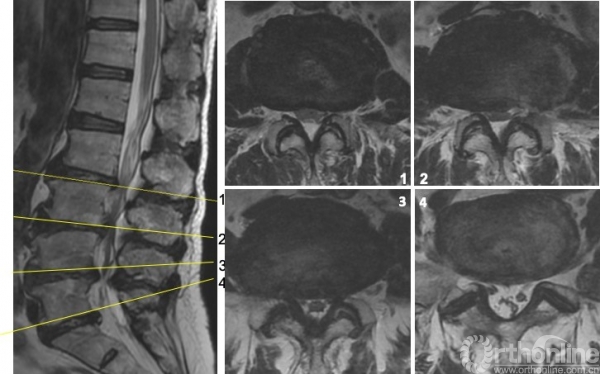

图4 术前MRI

解决方案:根据主诉、查体、辅助检查,术前需要明确致痛节段。首先,予患者局麻下行腰椎间盘造影(L2/3,L3/4,L4/5)(图5),在L3/4节段注射造影剂约2ml时,诱发出患者下腰痛症状,继续注射造影剂增加盘内压力后复制出左下肢放射痛,考虑该节段椎管空间狭小,遂予L4/5节段左椎间孔行L4出口神经根选择性神经根封闭,后患者左下肢疼痛明显缓解。

图5

患者约2天后左下肢疼痛复现,遂于局麻下为患者实施了L3/4经皮内镜下腰椎间盘切除术,术中发现神经根与纤维环粘连,松解粘连,术后患者疼痛得到完全缓解。左侧直腿抬高试验与股神经牵拉试验转阴。术前后核磁可见该节段神经压迫解除。(图6)

图6